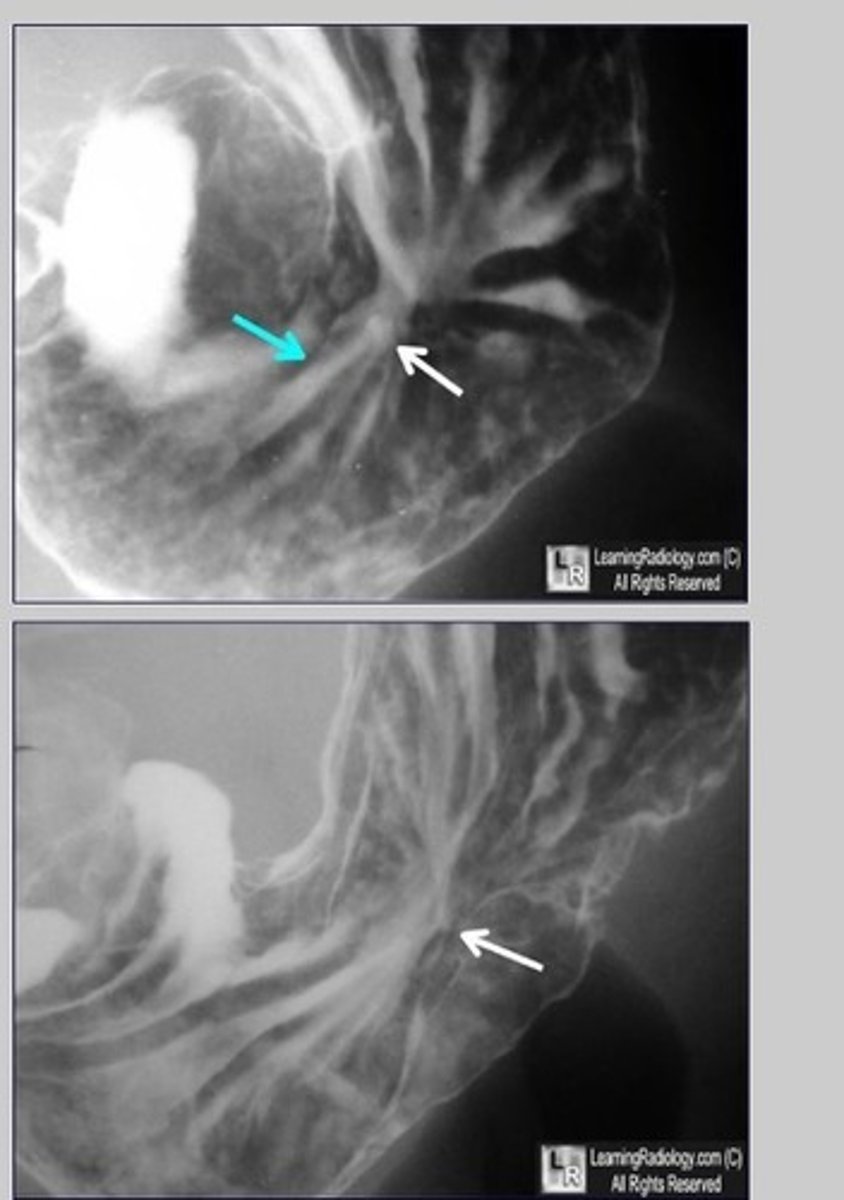

ulcer

Ulcer (pic 2)

ulcerative cancerous mass